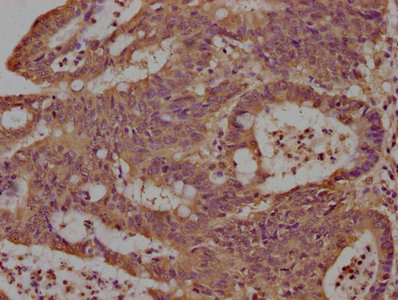

IHC image of PACO63335 diluted at 1:100 and staining in paraffin-embedded human colon cancer performed on a Leica BondTM system. After dewaxing and hydration, antigen retrieval was mediated by high pressure in a citrate buffer (pH 6.0). Section was blocked with 10% normal goat serum 30min at RT. Then primary antibody (1% BSA) was incubated at 4°C overnight. The primary is detected by a biotinylated secondary antibody and visualized using an HRP conjugated SP system.